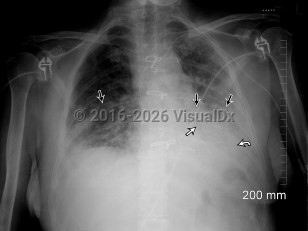

Fever, Cough, 50-59 year old Female

COVID-19